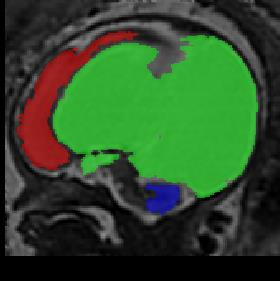

Limiting failures of machine learning systems is of paramount importance for safety-critical applications. In order to improve the robustness of machine learning systems, Distributionally Robust Optimization (DRO) has been proposed as a generalization of Empirical Risk Minimization (ERM). However, its use in deep learning has been severely restricted due to the relative inefficiency of the optimizers available for DRO in comparison to the wide-spread variants of Stochastic Gradient Descent (SGD) optimizers for ERM. We propose SGD with hardness weighted sampling, a principled and efficient optimization method for DRO in machine learning that is particularly suited in the context of deep learning. Similar to a hard example mining strategy in practice, the proposed algorithm is straightforward to implement and computationally as efficient as SGD-based optimizers used for deep learning, requiring minimal overhead computation. In contrast to typical ad hoc hard mining approaches, we prove the convergence of our DRO algorithm for over-parameterized deep learning networks with ReLU activation and a finite number of layers and parameters. Our experiments on fetal brain 3D MRI segmentation and brain tumor segmentation in MRI demonstrate the feasibility and the usefulness of our approach. Using our hardness weighted sampling for training a state-of-the-art deep learning pipeline leads to improved robustness to anatomical variabilities in automatic fetal brain 3D MRI segmentation using deep learning and to improved robustness to the image protocol variations in brain tumor segmentation. Our code is available at https://github.com/LucasFidon/HardnessWeightedSampler.